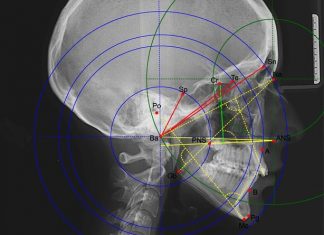

Снимок ТРГ в стоматологии экстра-класса!

Стоматология – достаточно обширная медицинская практика и область, где необходимо самым внимательным образом подойти к ...